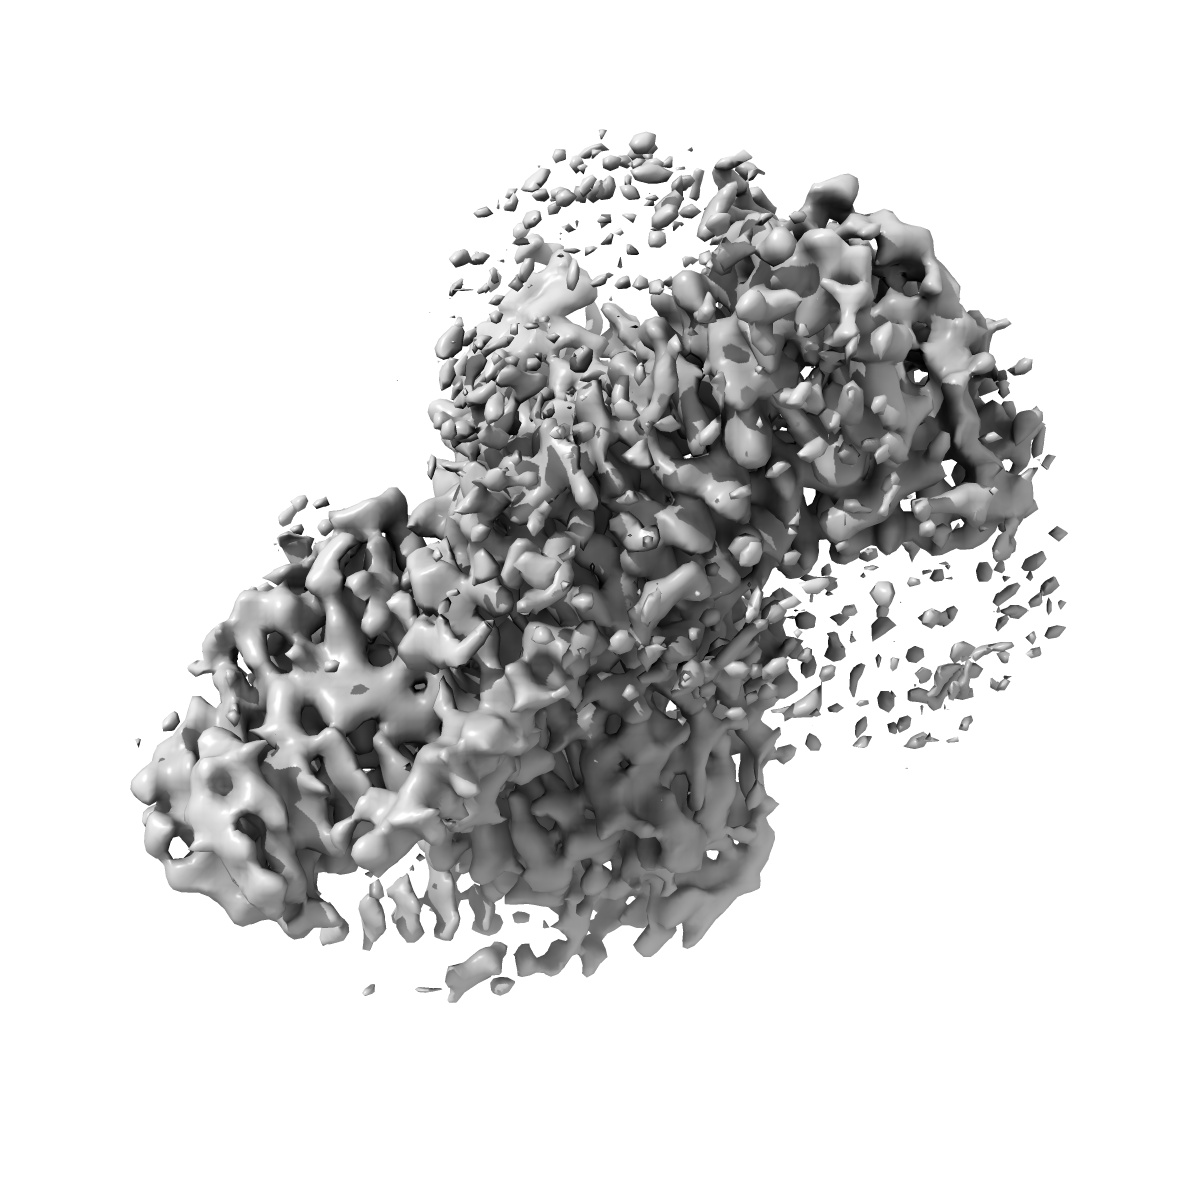

Sample: hTAAR1-bound T1AM in complex with Gs heterotrimer

Ligand recognition and G-protein coupling of trace amine receptor TAAR1.

(2023) Nature , 624 , 672 - 681